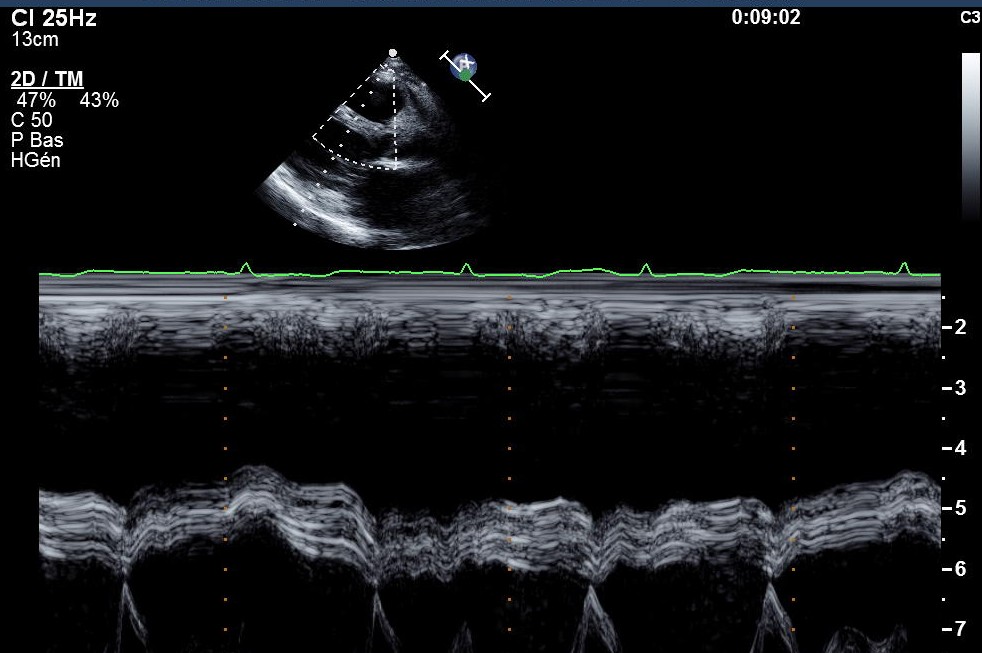

Sur cet exemple d’un patient présentant une PCC post tuberculeuse, l’aspect vibratile du septum en mode TM est très assez caractéristique :